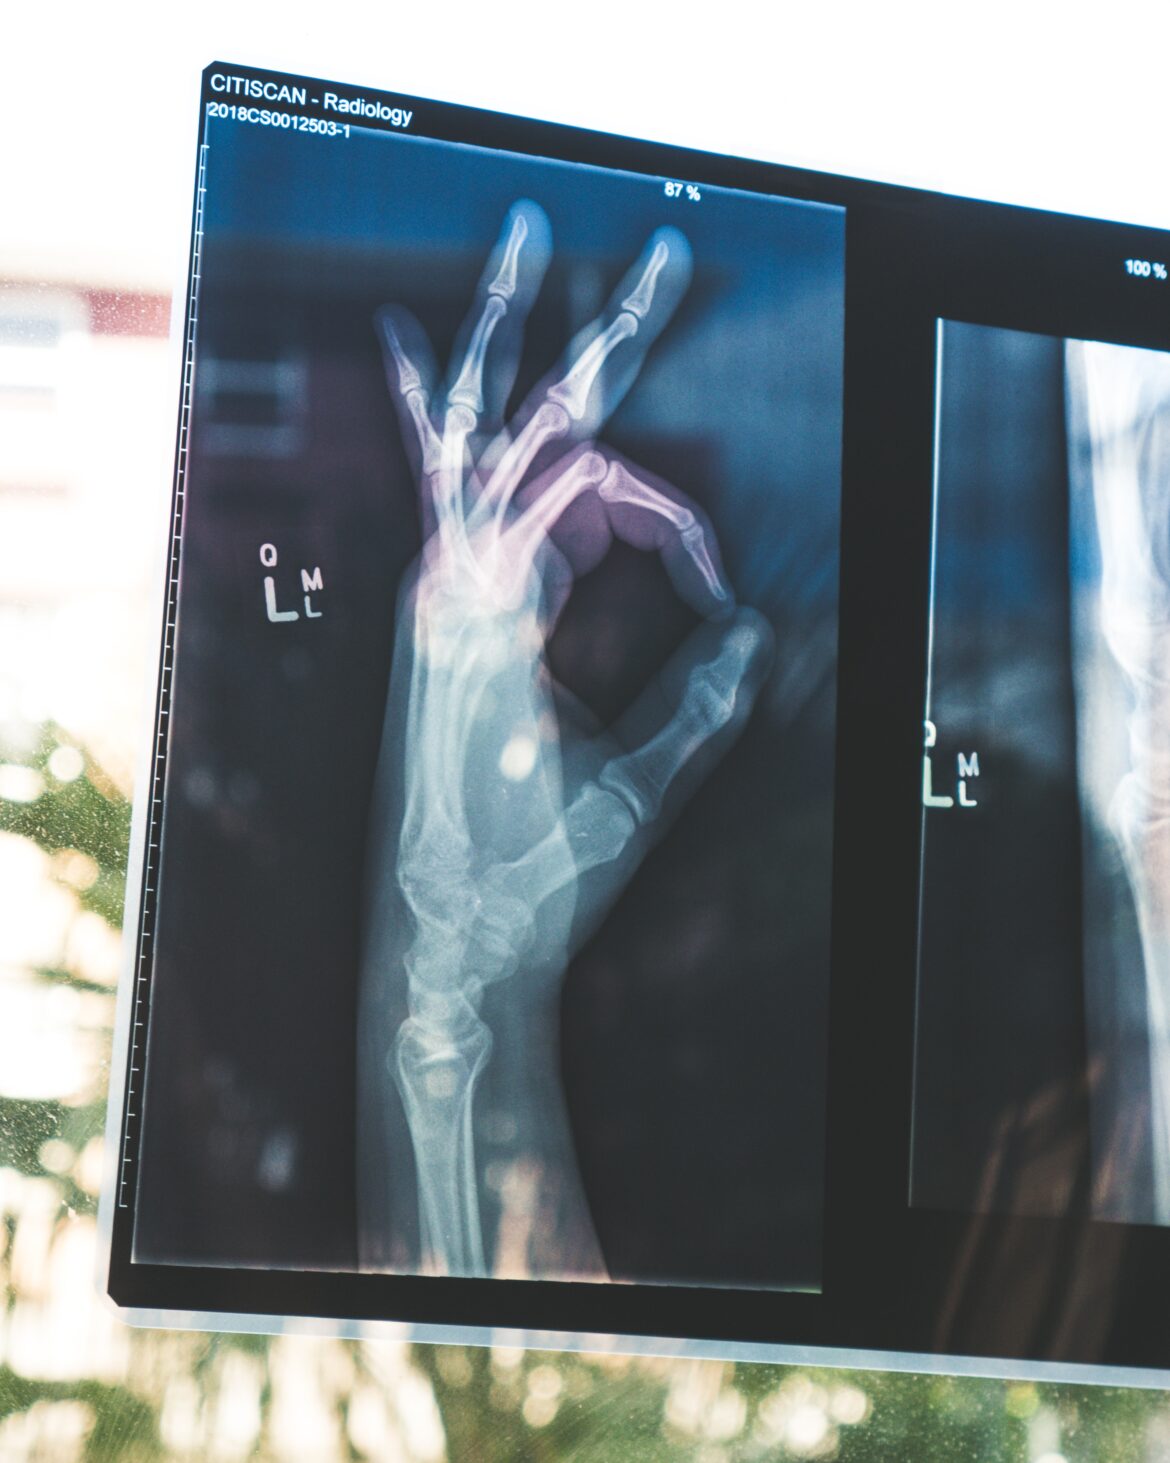

Durante su diagnostico es fácil que se llegue a confundir con hipotiroidismo, osteoporosis, displasia fibrosa y mieloma múltiple. Es por eso que los médicos para validar el diagnostico utilizan las siguientes pruebas:

- Rayos X.

- CT (tomografía computarizada)